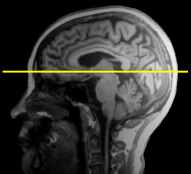

We pre-process the MRI images to use them in the proposed method. There are four steps in the preprocessing phase: (1) anterior commissure-posterior commissure correction using the 3D Slicer software111http://www.slicer.org/; (2) intensity inhomogeneity correction using N4ITK [39], an enhanced version of nonparametric nonuniform normalisation; (3) skull stripping using a pre-trained U-Net222https://github.com/iitzco/deepbrain to remove both the skull and the dura; and (4) rigid registration, which involves linearly aligning MRI images to the Colin27 template and resampling them to a size of 155×185×150155185150155\times 185\times 150 with a resolution of 1×1×1mm3111superscriptmm31\times 1\times 1~{}\mathrm{mm}^{3}. Figure 3 shows a sample of MRI image from ADNI-1 dataset on which the preprocessing is performed.

Figure 3: The visual representation of the preprocessing steps for an MRI sample. (a) A raw MRI image, (b) the MRI image with anterior commissure-posterior commissure correction (c) the MRI image with intensity inhomogeneity correction, and (4) skull stripped MRI image. The yellow line in (a) and (b) depicts the anterior commissure-posterior commissure line.